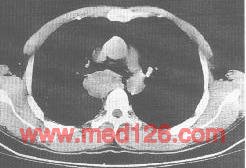

纵隔支气管囊肿。CT增强纵隔窗示气管分叉部右后下方见一类圆形无强化肿块。

①囊肿常位于隆突下区并延伸至纵隔右侧,也可位于气管旁或升主动脉周围。

②呈单房囊性肿块。密度均一,多呈水样密度,CT值0~20HU。某些囊肿内含有较多蛋白质,也可呈均一软组织密度CT值达20~50HU。边缘光滑,与周围结构分界清楚。

③增强检查,病变没有强化。对于平扫显示为高密度囊肿,病变无强化有助与其他实体性肿瘤鉴别。